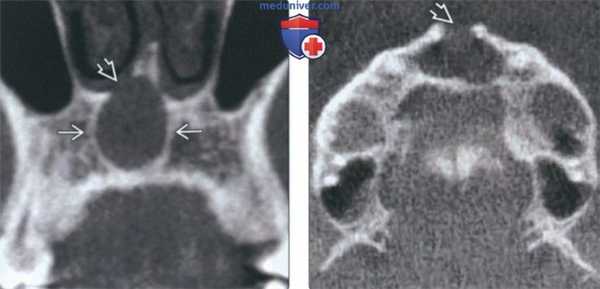

(Слева) На аксиальной КЛКТ определяется огромная КННП, приводящая к истончению и нарушению целостности язычной кортикальной пластинки.

(Справа) На корональной КЛКТ у этого же пациента определяется симметричное расширение носонебного канала, обусловленное огромной КННП. Дно полости рта слегка приподнято, но остается интактным. Верхний край образован кортикальной пластинкой, т.к. срез проходит спереди от носового отверстия канала. (Слева) На периапикальной рентгенограмме передних отделов верхней челюсти визуализируется крупная, хорошо отграниченная киста носонебного протока (КННП). Обратите внимание на ограничивающую кортикальную пластинку, размер которой >1 см, и гидравлическую экспансию. Наложение передней носовой ости придает кисте характерный вид сердца, типичный для образований большего размера.

(Справа) На аксиальной КЛКТ в передних отделах верхней челюсти определяется гиподенсный участок, отграниченный кортикальной пластинкой. КННП лежит между корнями центральных резцов верхней челюсти, но не затрагивает твердую пластинку.

(Слева) При аксиальной КТ в костном окне определяется равномерное концентрическое расширение резцового канала по средней линии в области альвеолярного отростка верхней челюсти. Расширенный участок ограничен кортикальной пластинкой. Эти изменения типичны для кисты носонебного протока.

(Справа) При аксиальной КТ в костном окне визуализируется киста сдвоенных носонебных протоков, разделенных очень тонкой костной перегородкой.